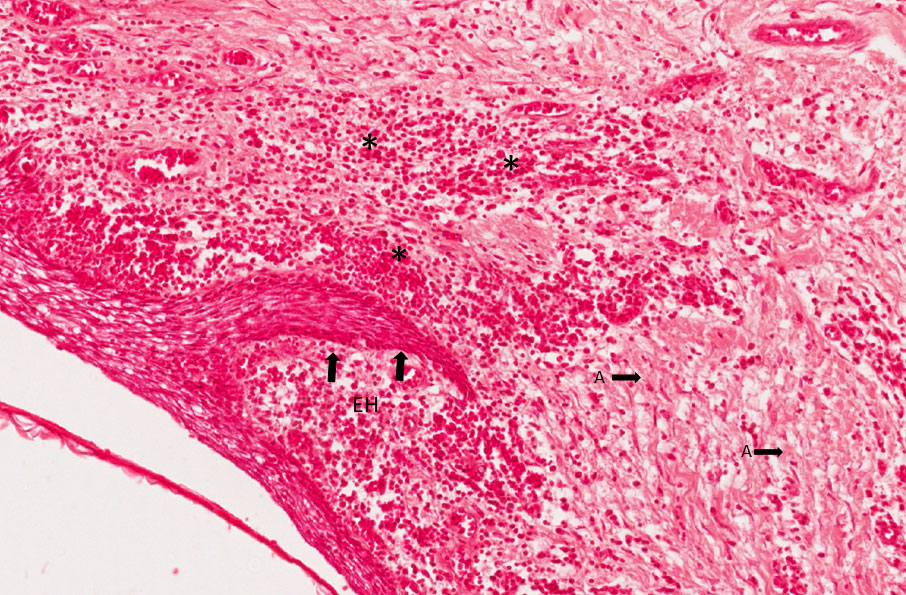

Observar a JAC integra, sem diminuição da crista óssea, tecido epitelial hiperplásico (EH - Figura 2), e eventos inflamatórios como as células (asteriscos – Figura 2), edema, hemorragia e hiperemia. Na área ocupada pelo infiltrado inflamatório crônico as fibras gengivais estão destruídas e no entorno observa-se algumas intactas (seta A – Figura 2).

Figura 2